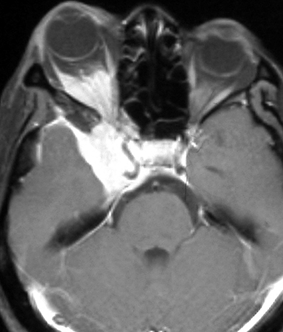

左は,造影剤を使ったガドリニウム増強MRIです。腫瘍が白く丸く見えます。右はフレア画像で,腫瘍の周囲の脳浮腫(脳のはれ)です。左前頭葉が,かなり強くはれています。この腫瘍は小さいのですが,脳のはれが強すぎるので手術摘出したほうがいいです。浮腫が悪化すると,てんかん発作や認知機能低下がでる可能性があります。

MRIでの髄膜腫の見え方は撮影の仕方によっていろいろです。左からT1強調画像,T2強調画像,フレア画像といいます。腫瘍の横に小さく白い領域がありますが,これは脳の腫れた部分で脳浮腫といいます。髄膜腫があると周囲に脳浮腫が生じることがあります。

最も見やすいのが,ガドリニウム造影剤を注射して撮影するものです。一般的に髄膜腫は造影剤で白く映し出されます。この腫瘍は左脳側にあります。MRIの軸面という輪切りの写真では左右が逆になりますから注意してください。脳を下から見た図になっています。MRIはいろいろな方向から腫瘍を見ることができますが,右は冠状断という正面から見た図です。よく見ると腫瘍の上と下のはじっこに線状に糸を引いたように造影される部分があります。これをテールサイン(しっぽのサイン)といいます。腫瘍が硬膜に沿って延びている可能性があることを示しています。